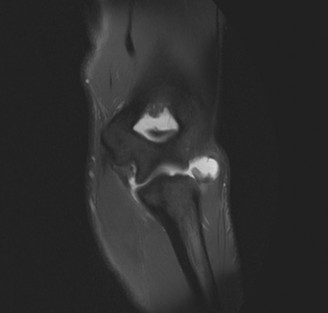

A patient is known to have a SLAP tear. An MRI shows a large cyst in the spinoglenoid notch. What additional finding on examination is the patient likely to display?

Explanation:

Weakness in external rotation. Compression at the spinoglenoid notch will affect only the infraspinatus as the suprascapular nerve has already innervated the supraspinatus by this point. Compression at the suprascapular notch will affect both the supraspinatus and the infraspinatus. Prolonged impingement on the suprascapular nerve by a spinoglenoid cyst can result in atrophy of the infraspinatus muscles. This would show up as weakness in external rotation on examination. These cysts are associated with SLAP lesions and are formed 40 by a one-way valve effect, where synovial fluid can exit the joint into the cyst but not drain spontaneously.